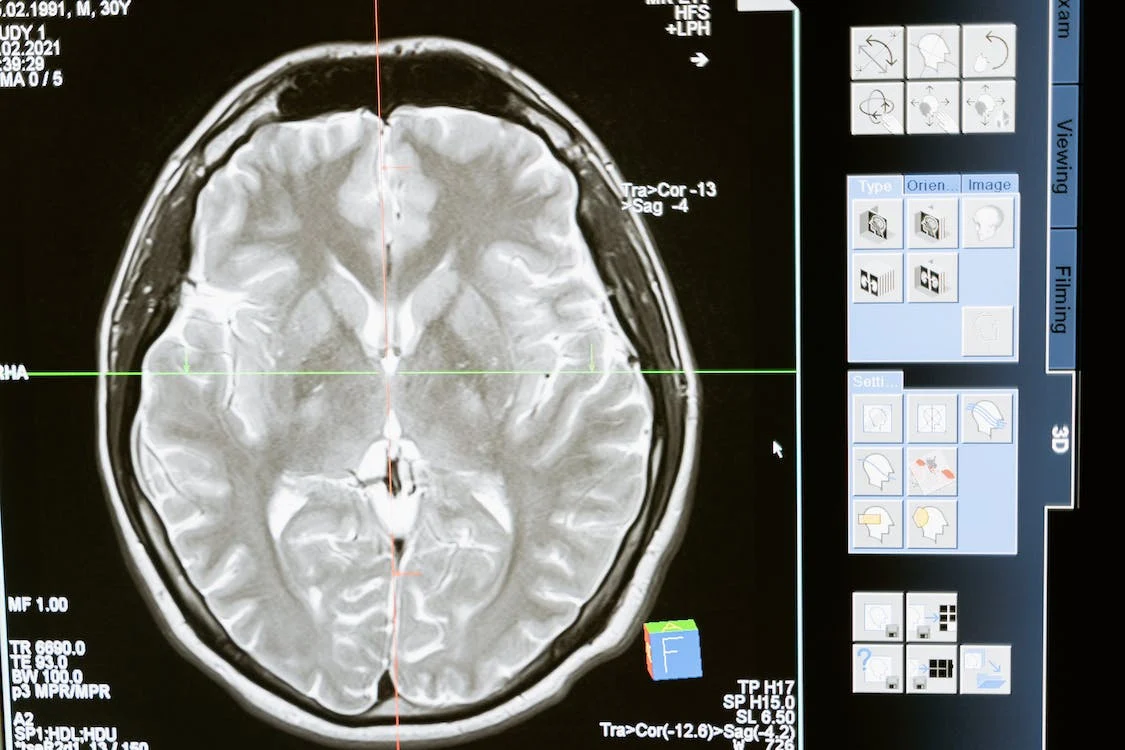

Brain Connectivity Disruptions May Explain Cognitive Deficits in People with Brain Injury